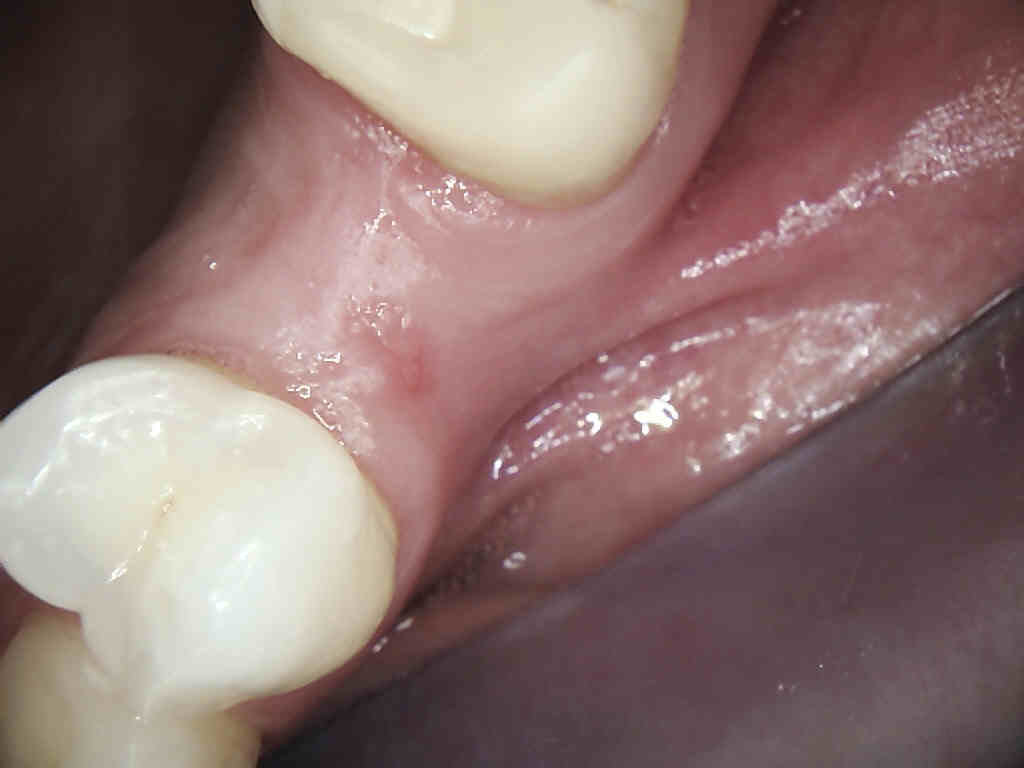

He received his Diploma in Implantology in 2016 from the University of Pretoria, which he passed with Distinction. He is also a member of the International Team for Implantology (ITI), which is based in Switzerland and offers members access to the latest research and cutting-edge techniques.